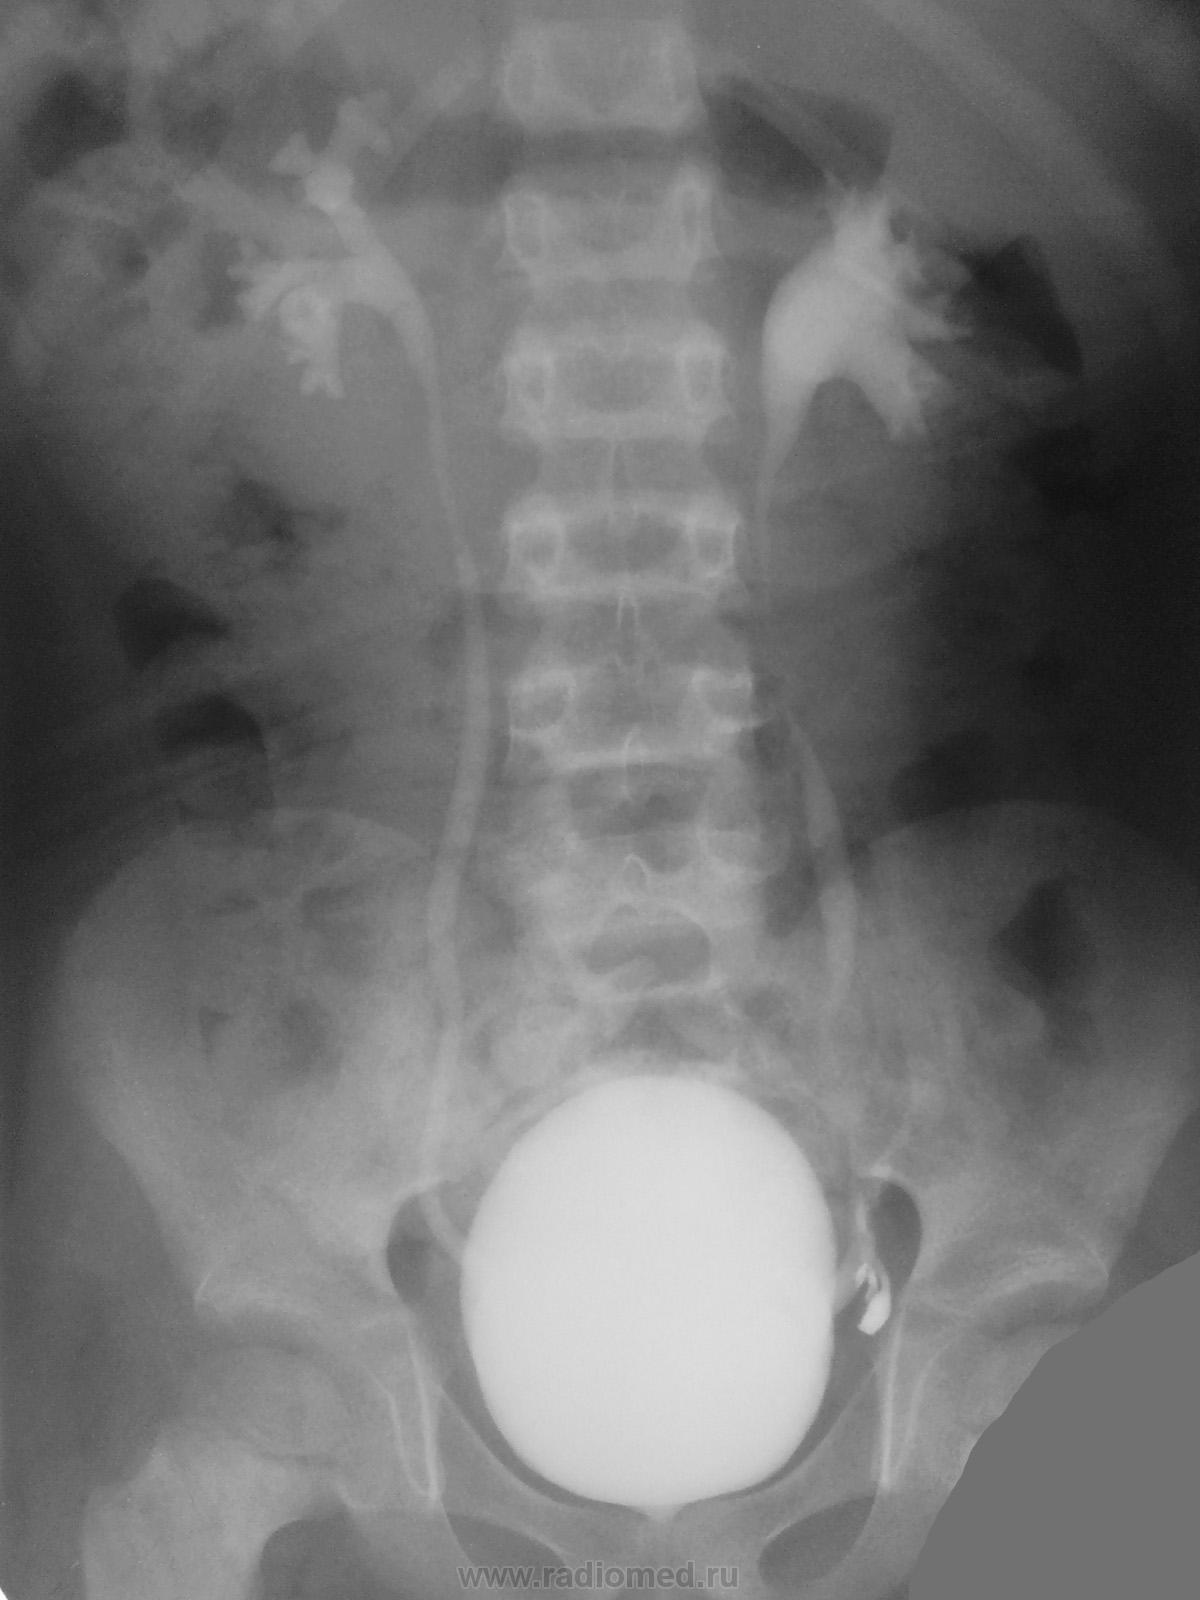

Медицинские изображения и примеры эксреторной цистографии